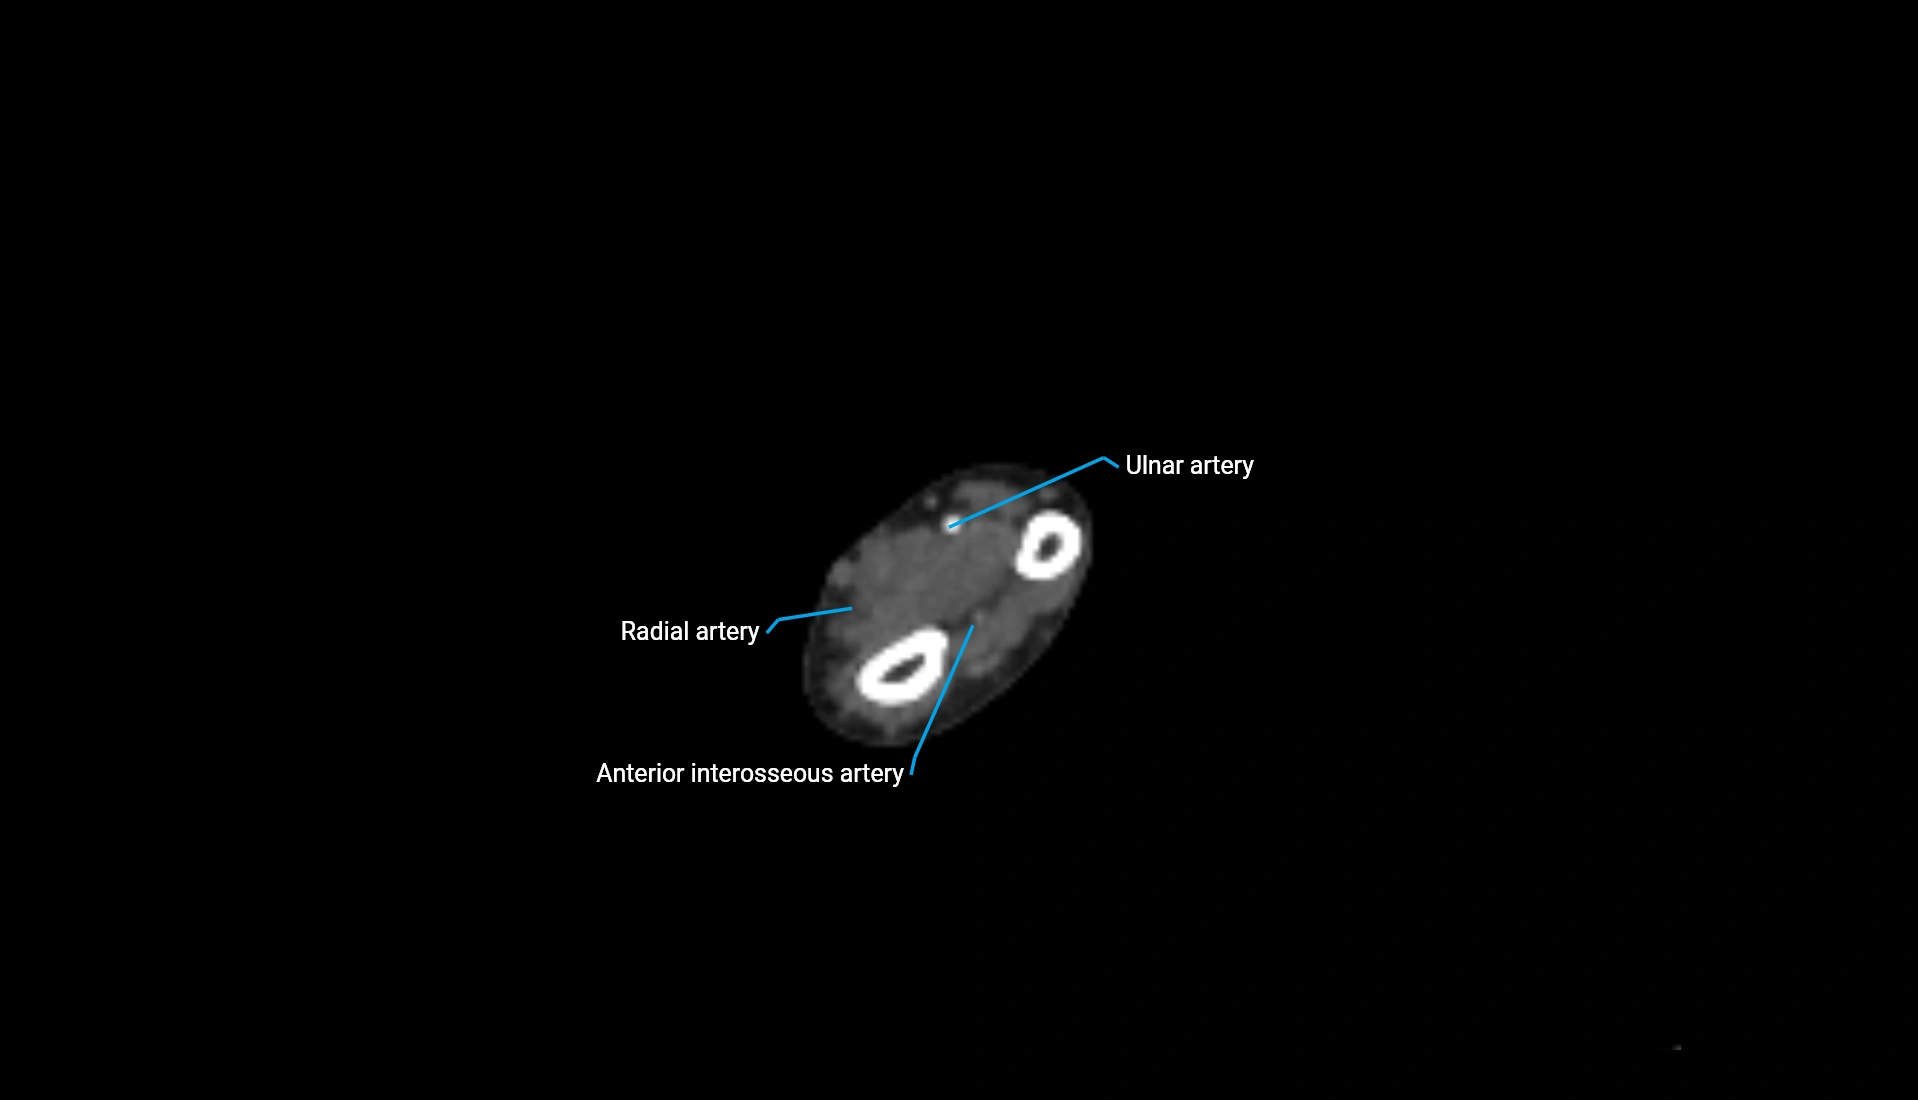

CT Appearance

Non-Contrast CT:

• Cortex: High-density, sharply defined

• Subchondral bone: Dense cancellous matrix

• Articular surface: Smooth concave contour articulating with the capitellum

• Excellent for evaluating bone integrity, alignment, and subtle fractures

Post-Contrast CT:

• Bone: No enhancement

• Joint capsule and synovium: Mild enhancement outlining the joint

• Improves contrast between soft tissues and bony margins

• Useful in detecting subtle joint abnormalities or postoperative changes